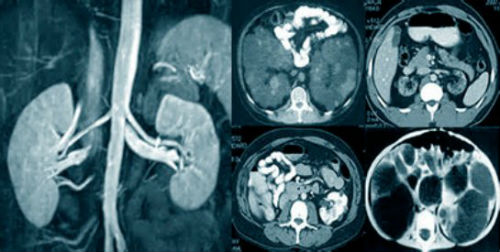

ΠΠ»Ρ Π²ΡΡΠ²Π»Π΅Π½ΠΈΡ Π·Π°Π±ΠΎΠ»Π΅Π²Π°Π½ΠΈΠΉ ΠΌΠΎΡΠ΅Π²ΡΠ΄Π΅Π»ΠΈΡΠ΅Π»ΡΠ½ΠΎΠΉ ΡΠΈΡΡΠ΅ΠΌΡ ΠΈΡΠΏΠΎΠ»ΡΠ·ΡΡΡΡΡ ΠΌΠ½ΠΎΠ³ΠΈΠ΅ Π²ΠΈΠ΄Ρ Π΄ΠΈΠ°Π³Π½ΠΎΡΡΠΈΠΊΠΈ. ΠΠ°ΠΈΠ±ΠΎΠ»Π΅Π΅ ΠΈΠ½ΡΠΎΡΠΌΠ°ΡΠΈΠ²Π½Π°Ρ ΠΈΠ· Π½ΠΈΡ β ΠΊΠΎΠΌΠΏΡΡΡΠ΅ΡΠ½Π°Ρ ΡΠΎΠΌΠΎΠ³ΡΠ°ΡΠΈΡ: Π±Π»Π°Π³ΠΎΠ΄Π°ΡΡ Π²ΡΡΠΎΠΊΠΎΠΌΡ ΡΠ°Π·ΡΠ΅ΡΠ΅Π½ΠΈΡ ΠΌΠ΅ΡΠΎΠ΄ ΠΏΠΎΠ·Π²ΠΎΠ»ΡΠ΅Ρ ΠΎΠ±Π½Π°ΡΡΠΆΠΈΡΡ ΠΊΠ°ΠΌΠ½ΠΈ ΠΌΠ΅Π½Π΅Π΅ 1 ΠΌΠΌ. Π‘ΠΊΠ°Π½ΠΈΡΠΎΠ²Π°Π½ΠΈΠ΅ ΠΏΡΠΈ ΠΠ’ Π²ΡΠΏΠΎΠ»Π½ΡΠ΅ΡΡΡ Ρ ΡΠ°Π·Π½ΡΡ ΡΠΎΡΠ΅ΠΊ ΠΈ ΠΏΠΎΠ΄ ΡΠ°Π·Π½ΡΠΌΠΈ ΡΠ³Π»Π°ΠΌΠΈ, Π² ΡΠ΅Π·ΡΠ»ΡΡΠ°ΡΠ΅ ΡΠ΅Π³ΠΎ ΡΠΎΡΠΌΠΈΡΡΡΡΡΡ ΡΡΠ΅Ρ ΠΌΠ΅ΡΠ½ΡΠ΅ ΠΈΠ·ΠΎΠ±ΡΠ°ΠΆΠ΅Π½ΠΈΡ ΠΏΠΎΡΠ»ΠΎΠΉΠ½ΡΡ ΡΡΠ΅Π·ΠΎΠ² ΠΈΡΡΠ»Π΅Π΄ΡΠ΅ΠΌΠΎΠ³ΠΎ ΠΎΡΠ³Π°Π½Π°.

ΠΠ’ ΠΏΠΎΡΠ΅ΠΊ ΠΈ ΠΌΠΎΡΠ΅ΡΠΎΡΠ½ΠΈΠΊΠΎΠ² β ΡΡΠΎ Π²ΠΈΠ΄ ΠΎΠ±ΡΠ»Π΅Π΄ΠΎΠ²Π°Π½ΠΈΡ, Π²ΡΡΠ²Π»ΡΡΡΠΈΠΉ ΡΡΠ½ΠΊΡΠΈΠΎΠ½Π°Π»ΡΠ½ΡΠ΅ ΠΈ ΠΎΡΠ³Π°Π½ΠΈΡΠ΅ΡΠΊΠΈΠ΅ ΠΏΠ°ΡΠΎΠ»ΠΎΠ³ΠΈΡΠ΅ΡΠΊΠΈΠ΅ ΠΈΠ·ΠΌΠ΅Π½Π΅Π½ΠΈΡ Π² ΠΌΠΎΡΠ΅Π²ΡΠ΄Π΅Π»ΠΈΡΠ΅Π»ΡΠ½ΠΎΠΉ ΡΠΈΡΡΠ΅ΠΌΠ΅.

ΠΠ»Π°Π³ΠΎΠ΄Π°ΡΡ ΡΠΎΠΌΠΎΠ³ΡΠ°ΡΠΈΠΈ ΡΠΏΠ΅ΡΠΈΠ°Π»ΠΈΡΡ ΠΌΠΎΠΆΠ΅Ρ Π΄Π°ΡΡ ΠΎΡΠ΅Π½ΠΊΡ ΡΡΠ½ΠΊΡΠΈΠΎΠ½ΠΈΡΠΎΠ²Π°Π½ΠΈΡ ΠΈ Π°Π½Π°ΡΠΎΠΌΠΈΡΠ΅ΡΠΊΠΎΠΌΡ ΡΠΎΡΡΠΎΡΠ½ΠΈΡ ΠΏΠΎΡΠ΅ΠΊ ΠΈ ΠΌΠΎΡΠ΅ΡΠΎΡΠ½ΠΈΠΊΠΎΠ². ΠΠΎΠ»ΡΡΠ΅Π½Π½ΡΠ΅ ΠΈΠ·ΠΎΠ±ΡΠ°ΠΆΠ΅Π½ΠΈΡ ΠΏΠΎΠ·Π²ΠΎΠ»ΡΡΡ ΡΠ²ΠΈΠ΄Π΅ΡΡ ΡΠ»Π΅Π΄ΡΡΡΠΈΠ΅ ΠΏΠ°ΡΠΎΠ»ΠΎΠ³ΠΈΠΈ:

Π ΡΠ΅Π·ΡΠ»ΡΡΠ°ΡΠ΅ ΠΊΠΎΠΌΠΏΡΡΡΠ΅ΡΠ½ΠΎΠΉ ΡΠΎΠΌΠΎΠ³ΡΠ°ΡΠΈΠΈ ΠΏΠΎΠ»ΡΡΠ°ΡΡ ΠΏΠΎΡΠ»ΠΎΠΉΠ½ΡΠ΅ ΠΈΠ·ΠΎΠ±ΡΠ°ΠΆΠ΅Π½ΠΈΡ ΠΏΠΎΡΠ΅ΠΊ Π² ΠΏΠΎΠΏΠ΅ΡΠ΅ΡΠ½ΠΎΠΉ ΠΏΠ»ΠΎΡΠΊΠΎΡΡΠΈ. ΠΠΎ ΡΠ½ΠΈΠΌΠΊΠ°ΠΌ ΠΎΡΠ΅Π½ΠΈΠ²Π°ΡΡ ΡΠ°Π·ΠΌΠ΅ΡΡ, ΡΠ°ΡΠΏΠΎΠ»ΠΎΠΆΠ΅Π½ΠΈΠ΅, ΡΡΡΡΠΊΡΡΡΡ ΠΎΡΠ³Π°Π½ΠΎΠ². ΠΠ’ ΠΏΠΎΠ·Π²ΠΎΠ»ΡΠ΅Ρ Π΄ΠΈΠ°Π³Π½ΠΎΡΡΠΈΡΠΎΠ²Π°ΡΡ Π°Π½ΠΎΠΌΠ°Π»ΠΈΠΈ ΡΠ°Π·Π²ΠΈΡΠΈΡ ΠΌΠΎΡΠ΅Π²ΡΠ΄Π΅Π»ΠΈΡΠ΅Π»ΡΠ½ΠΎΠΉ ΡΠΈΡΡΠ΅ΠΌΡ, ΡΠ²Π΅Π»ΠΈΡΠ΅Π½ΠΈΠ΅ Π»ΠΈΠΌΡΠ°ΡΠΈΡΠ΅ΡΠΊΠΈΡ ΡΠ·Π»ΠΎΠ² Π·Π°Π±ΡΡΡΠΈΠ½Π½ΠΎΠ³ΠΎ ΠΏΡΠΎΡΡΡΠ°Π½ΡΡΠ²Π°, Π΄ΠΎΠ±ΡΠΎ- ΠΈ Π·Π»ΠΎΠΊΠ°ΡΠ΅ΡΡΠ²Π΅Π½Π½ΡΠ΅ ΠΎΠ±ΡΠ°Π·ΠΎΠ²Π°Π½ΠΈΡ, Π³ΠΈΠ΄ΡΠΎΠ½Π΅ΡΡΠΎΠ·, ΡΡΠ΅Π½ΠΎΠ· ΠΌΠΎΡΠ΅ΡΠΎΡΠ½ΠΈΠΊΠΎΠ², ΠΊΠ°ΠΌΠ½ΠΈ, ΠΏΡΠΈΠ·Π½Π°ΠΊΠΈ Π²ΠΎΡΠΏΠ°Π»Π΅Π½ΠΈΡ, Π°Π±ΡΡΠ΅ΡΡΡ, ΠΏΠΎΡΠ°ΠΆΠ΅Π½ΠΈΠ΅ ΡΠΎΡΡΠ΄ΠΎΠ² ΠΈ Π΄ΡΡΠ³ΠΈΠ΅ ΠΏΠ°ΡΠΎΠ»ΠΎΠ³ΠΈΠΈ.